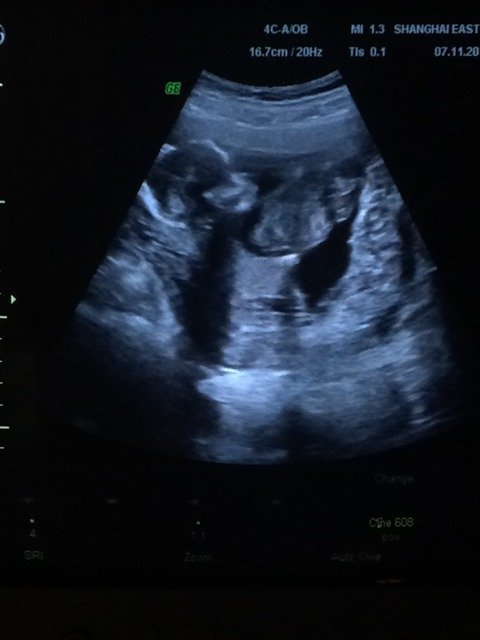

怎么看上去好奇怪 怎么看上去好奇怪 点击展开 wanan_mini 2014-11-07 10:11 为您推荐: 其他回答 看着是正常的吧应该, 文斯6 2014-11-07 20:41 你好,看着没有异常啊,大小大概是在3个月左右吧。按时产检啊, 文斯6 2014-11-07 12:19 不奇怪,医生怎么说的 陌路了 2014-11-07 11:10 像我们这种业余的看都觉得奇怪 俊杉麻麻 2014-11-07 10:33 都是这样吧 顺其自然_HG0I 2014-11-07 10:31 加载更多 相关问题 好奇怪哦!帮帮忙 好奇怪的体温 这个是什么树根看上去好奇怪